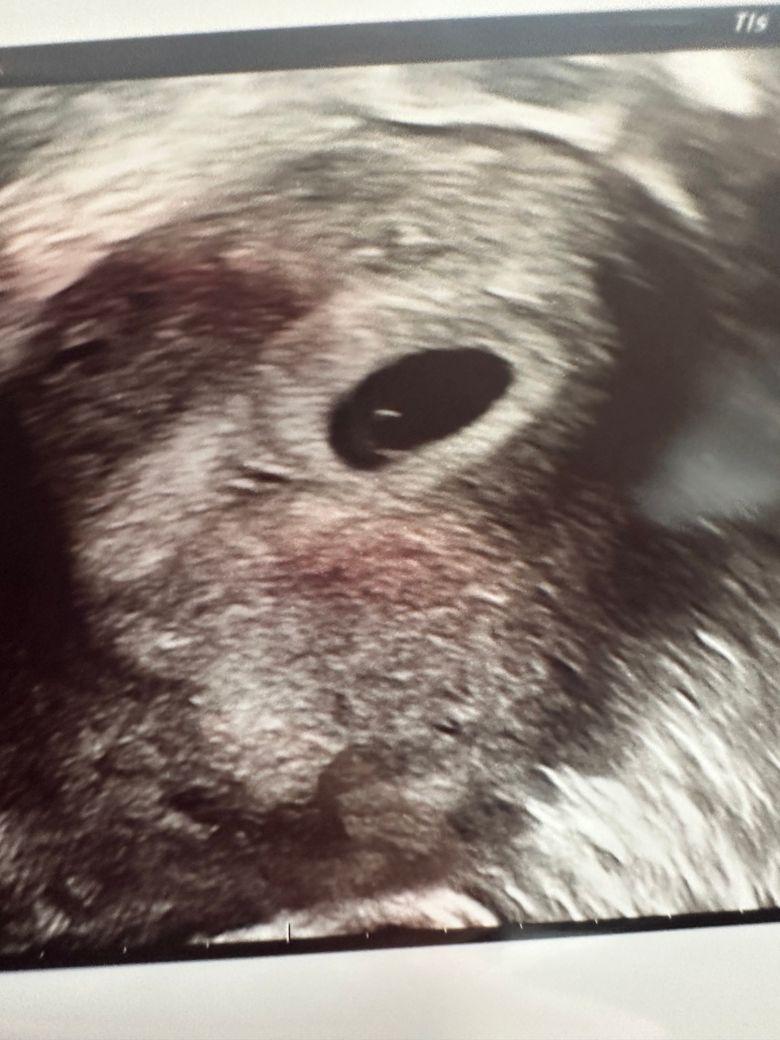

4월12일에(5주1일) 첫 초음파로 아기집 보고왔는데 이때 선생님이 담주에 오면 심장소리랑 들을수있다해서 오늘 갔다왔거든요

오늘 갔다왔는데 아기집 커지고 난황 봤어요

근데 심장소리와 아기는 못 봤네요 ㅠㅠ

6주1일에 심장소리 못듣는 사람 많은가요? ㅠㅠ 쌤이 불안하면 3-4일 뒤에 와보고 아니면 담주에 오라했는데 ㅠㅠ 수요일에 다시 가보려구요 그땐 심장소리랑 아기 볼 수 있을까요? ㅠㅠ 그리고 아기집 크기랑 난황크기 어때보일까요? 둘다 넘 커보이지 않나요? 괜찮은건가요??

• 1번 째 사진

• 2번 째 사진

특히 아기집(gestational sac)과 난황(yolk sac)이 잘 보이고 크기나 모양이 정상이라면, 임신이 건강하게 진행 중일 가능성이 높습니다. 의사 선생님이 3, 4일 후 또는 다음 주에 다시 보자고 하신 건 자연스러운 경과 관찰 방법이에요.

아기집과 난황의 크기에 대해서는 정확한 수치를 확인해야 좀 더 정확히 말씀드릴 수 있지만, 보통 임신 6주 초반이라면 아기집은 약 1.52cm, 난황은 3-6mm 사이로 보이는 경우가 많아요. 너무 크거나 이상하게 보였다면 의사 선생님이 따로 말씀하셨을 거예요.